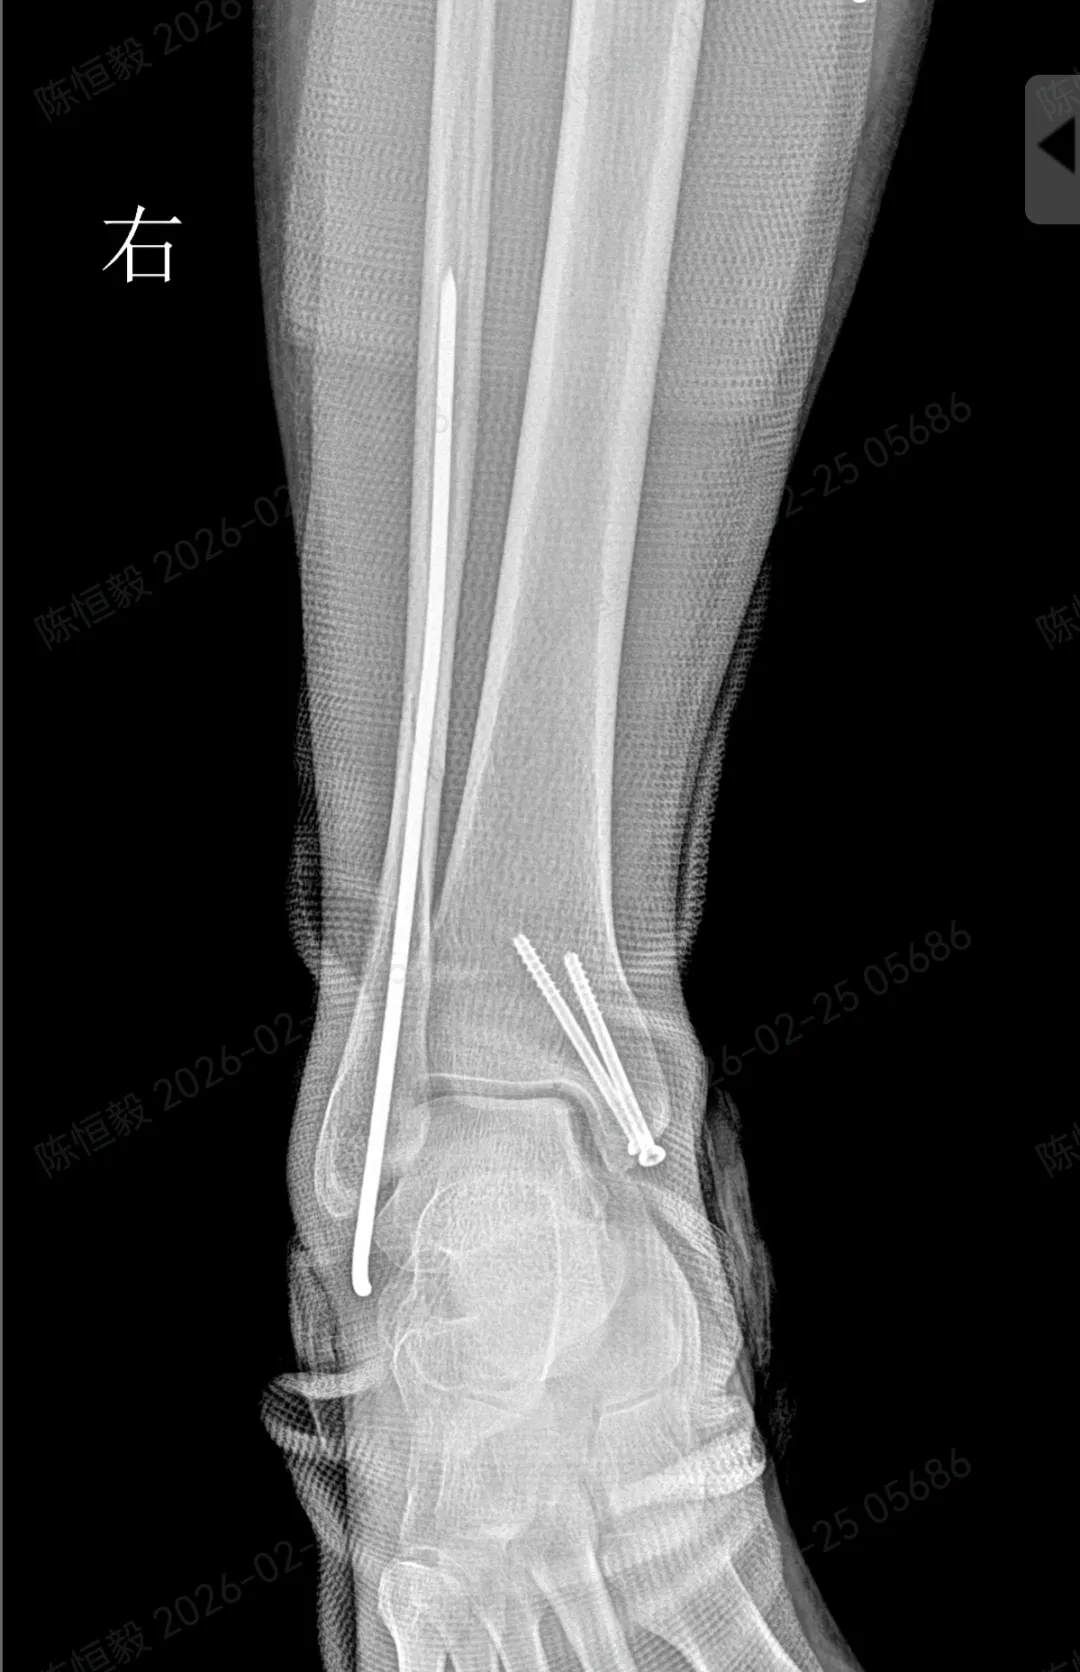

针对王女士的踝关节骨折情况,由副主任医师陈涛主刀,足踝外科团队为其实施了关节镜辅助下机器人导航微创闭合复位内固定术

• 通过 5 毫米小切口将关节镜探入关节腔内,清理腔内淤血与致炎因子,清晰观察骨折块移位及关节软骨损伤情况;

• 在关节镜直视下,使用微创器械将骨折块复位至解剖位置,恢复关节面平整;

• 依托机器人导航系统,规划螺钉置入通道,避开关节面与重要组织;

• 最后通过另外两个 5 毫米的小孔置入空心螺钉,完成骨折端的稳定固定。

整个手术仅通过三个 5 毫米的小切口完成,最大程度降低了手术创伤。

对于踝关节骨折的诊疗而言,关节面复位的精准度直接关系到远期恢复效果,若复位存在偏差,可能增加创伤性关节炎、慢性疼痛、关节功能障碍等问题的发生概率。

本次诊疗中,在关节镜直视下确保骨折部位实现解剖复位,同时对检查中发现的合并软骨损伤进行了同步处理,为关节的后续恢复提供了保障。